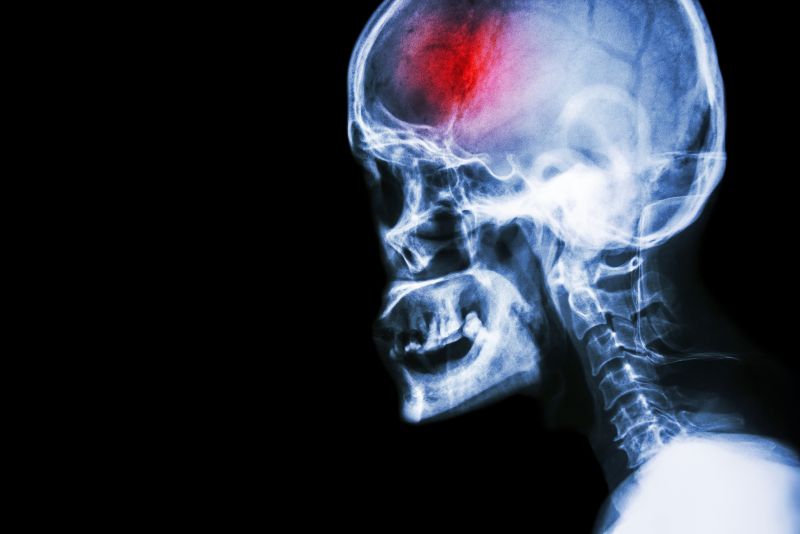

A stroke (previously known as a cerebrovascular accident) when there is a decreased flow of blood to the brain from either a blockage in the blood vessels that supply the brain (ischemic stroke), or a bleed from the blood vessels that supply the brain (hemorrhagic stroke). When the blood flow to the brain is blocked it prevents the brain from getting the needed oxygen and nutrients to function. Without oxygen the brain cells can be permanently damaged or die and the physical and mental functions related to that area of the brain will be affected. A stroke is a medical emergency and rapid treatment is crucial to decreasing the damage caused by a stroke.

- Ischemic stroke: a stroke that is caused by a blockage (clot) that disturbs the blood flow to the brain.

- Hemorrhagic stroke: a stroke that is caused by a bleed that disturbs the blood flow to the brain and puts pressure on the surrounding tissue.

Computed Tomography (CT) scan and/or Magnetic Resonance Imaging (MRI) scan: These tests are done on your brain and used to locate the exact location of the stroke and to determine if it has been caused by a blockage or a bleed. These tests can also help rule out other conditions that may be causing symptoms, such as an infection or a brain tumour